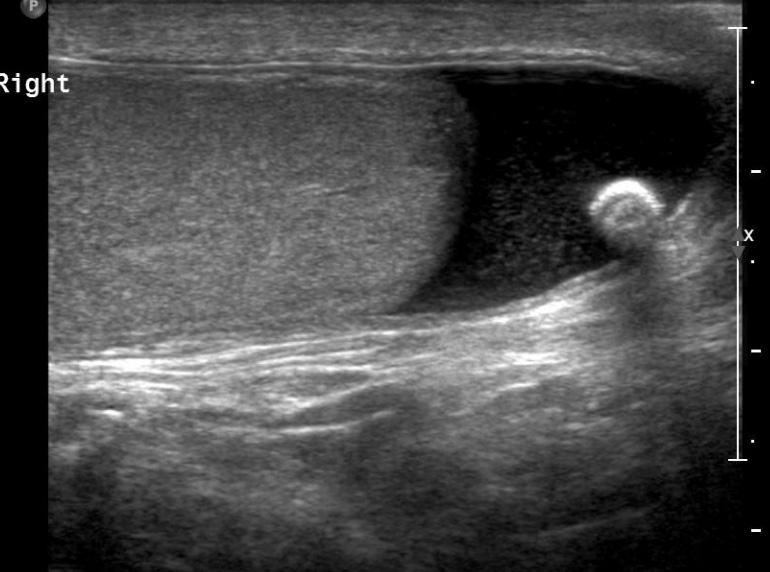

most common fluid collection of the testicle

Hydrocele

serious fluid between the tunica vaginalis